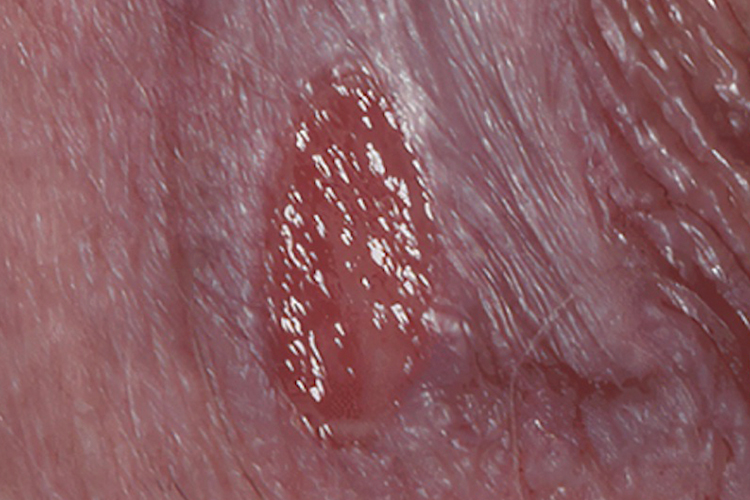

女婴儿外阴阴道炎主要症状为阴道分泌脓性分泌物,女婴儿因外阴痛痒而哭闹、烦躁不安或用手搔抓外阴。检查可见外阴、阴蒂、尿道口、阴道口黏膜充血、水肿,病情严重者,外阴表面可见溃疡甚至发生阴唇粘连。

女婴儿尿布皮炎可见会阴部至腹股沟及下腹的皮损呈大片潮红,亦可发生斑丘疹和丘疹,边缘清楚,皮损形态与尿布包扎范围一致。